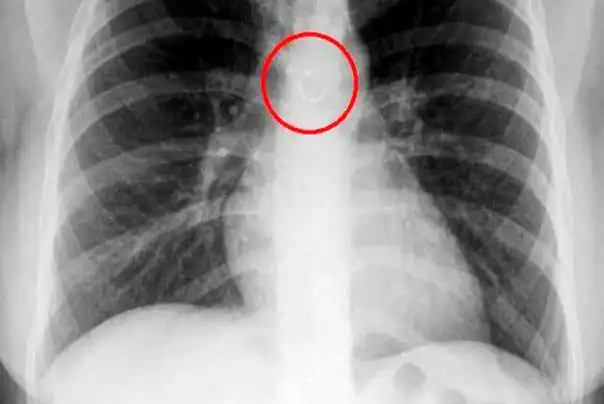

Očekivala je da će rendgenski snimak otkriti problem, ali ono što definitivno nije očekivala jeste pirsing na nosu koji je završio u njenim plućima!

Dejanirin početni šok ubrzo se pretvorio u strah za njen život, jer su joj lekari rekli da je kružna metalna šipka samo 0,5 milimetara od njene aorte.

pirsing u plućima

pirsing u plućima Dejanire